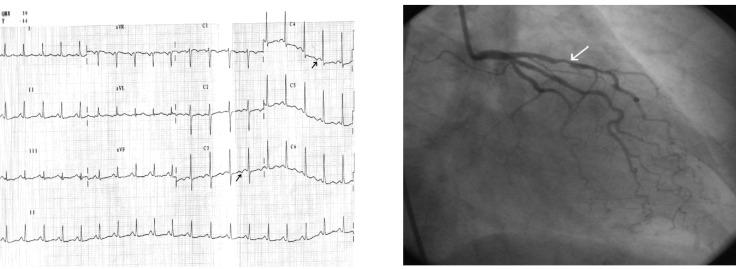

心绞痛患者的心电图特征。

The electrocardiographic profile of patients with angina pectoris.

Angina pectoris is a common disabling disorder and a clinical syndrome, caused by myocardial ischemia; an imbalance between myocardial oxygen supply and myocardial oxygen consumption. Thus, ischemia produces a typical series of events such as metabolic and biochemical alterations which lead to impaired ventricular relaxation and diastolic dysfunction, impaired systolic function, and electrocardiographic abnormalities and painful symptoms of angina. Transmembrane ionic currents are responsible for the cardiac potentials that are recorded as the electrocardiogram (ECG). The electrocardiographic profile of patients with angina pectoris is variate. The electrocardiogram provides critical information for both diagnosis and prognosis, particularly when a tracing is obtained during the episodes of pain. A completely normal electrocardiogram does not exclude the possibility of acute coronary syndrome. Serial ECG tracings improve the clinician's ability to diagnose acute and chronic coronary syndromes. The ECG may assist in clarifying the differential diagnosis if taken in the presence of pain. The resting ECG also has an important role in risk stratification. Exercise ECG is more sensitive and specific than the resting ECG as far as myocardial ischemia detection is concerned, and it represents the test of choice which helps identifying inducible ischemia in the majority of patients suspected of stable angina.

摘要